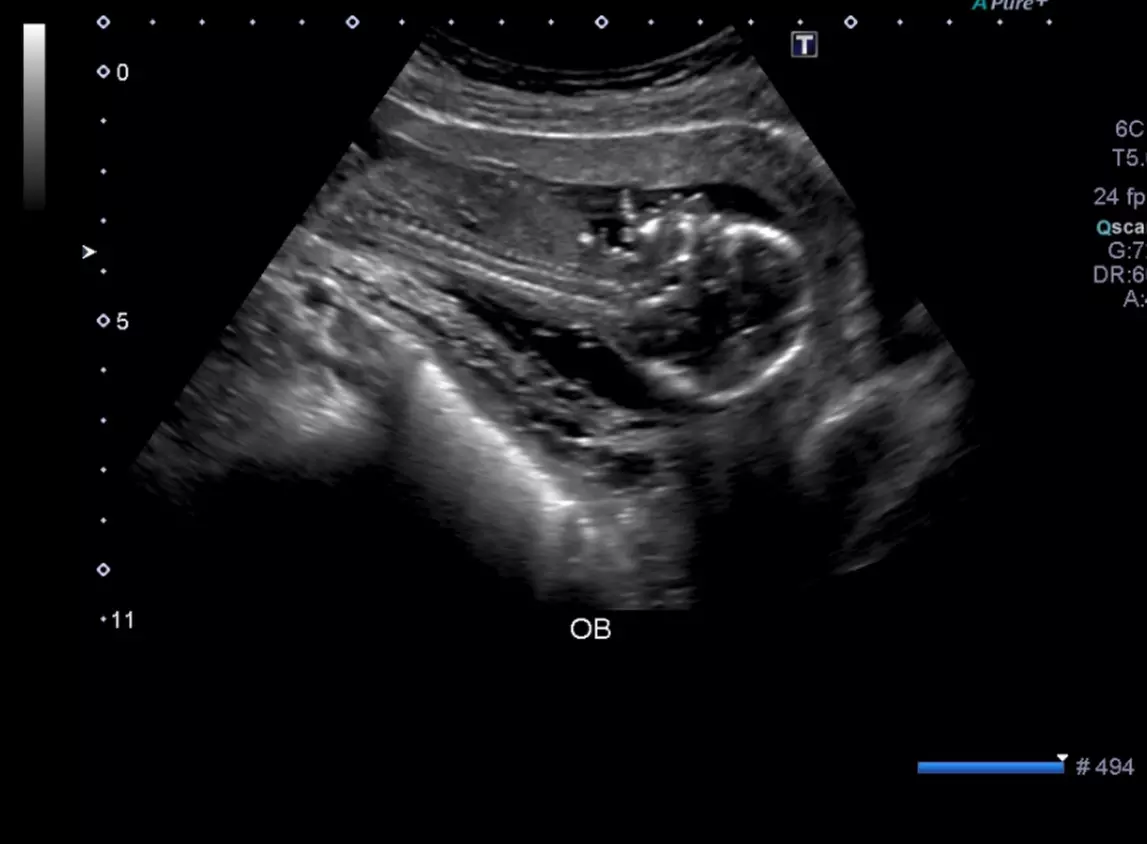

Up to 53% Off on Ultrasound at Luxury Therapy Medical Center

Ultrasound service in a luxury ultrasound center like you and your baby deserve, certified RDMS with + 10 years of experience.

2-Complete OB Ultrasound with more than 10 HD pictures, baby face details, placenta location, amniotic fluid index, fetal presentation, baby weight and heart beat.